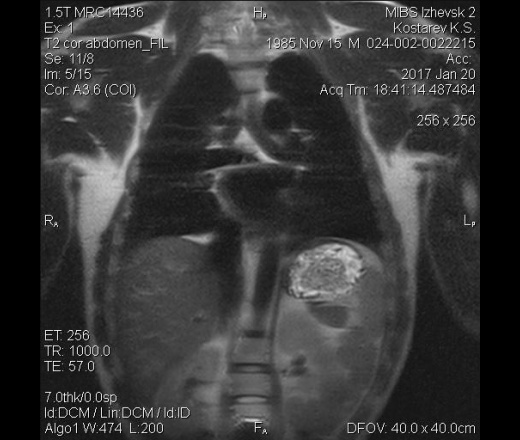

Приветствую уважаемые врачи! Недавно проходил мрт по поводу болей в спине. В районе селезенки было замечено не понятное образование, не могу определиться нужно ли мне беспокоиться и делать узи+кт или это просто добавочная селезенка?

Заключение -протрузии диска th7\th8 0.2mm  l5\s1 0.3mm

На томогрммах видна киста в левой почке

а на аксиалах по задней поверхности разве не добавочная долька?

почка и кишки на аксиалах.